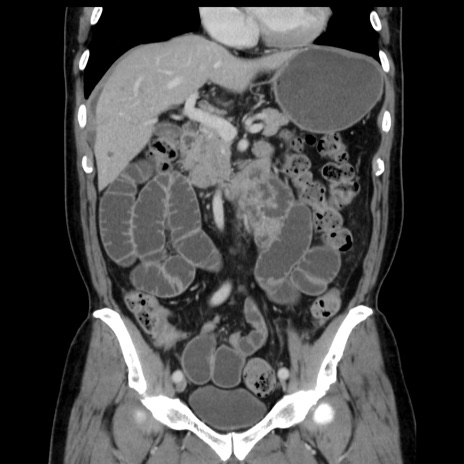

症例16(冠状断像)

【症例】 70歳代男性

【主訴】 腹痛、嘔吐

【現病歴】 約1ヶ月前より間欠的に腹痛と嘔吐あり、当院消化器内科を受診したところCTで多発する肝臓のLDAを指摘され、精査中であった。以降は消化器症状は安定していたが、2日前より嘔気と腹痛があり、同日より排便・排ガスが消失した。改善認めず、 本日、救急外来を受診した。

【既往歴】 大腸ポリープ切除後。

【身体所見】意識清明・会話良好、BT 36.3℃、BP 127/80mmHg、 P 80bpm、腹部:膨満あり、平坦・軟、上腹部正中および下腹部正中に圧痛あり、反跳痛なし、筋性防御なし。

【データ】WBC 7200、CRP 0.77